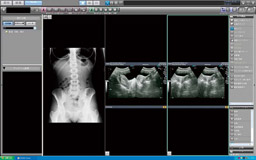

【REGIUS Unitea画面】

検査履歴を,日付別とモダリティ別に表示できるため,過去の検査の情報を把握しやすいと泉屋院長は評価する。異なるモダリティの画像も並べて表示できるため,一度に多くの情報を取得することができる。紹介先には, A4判で紙出力して渡している。 |